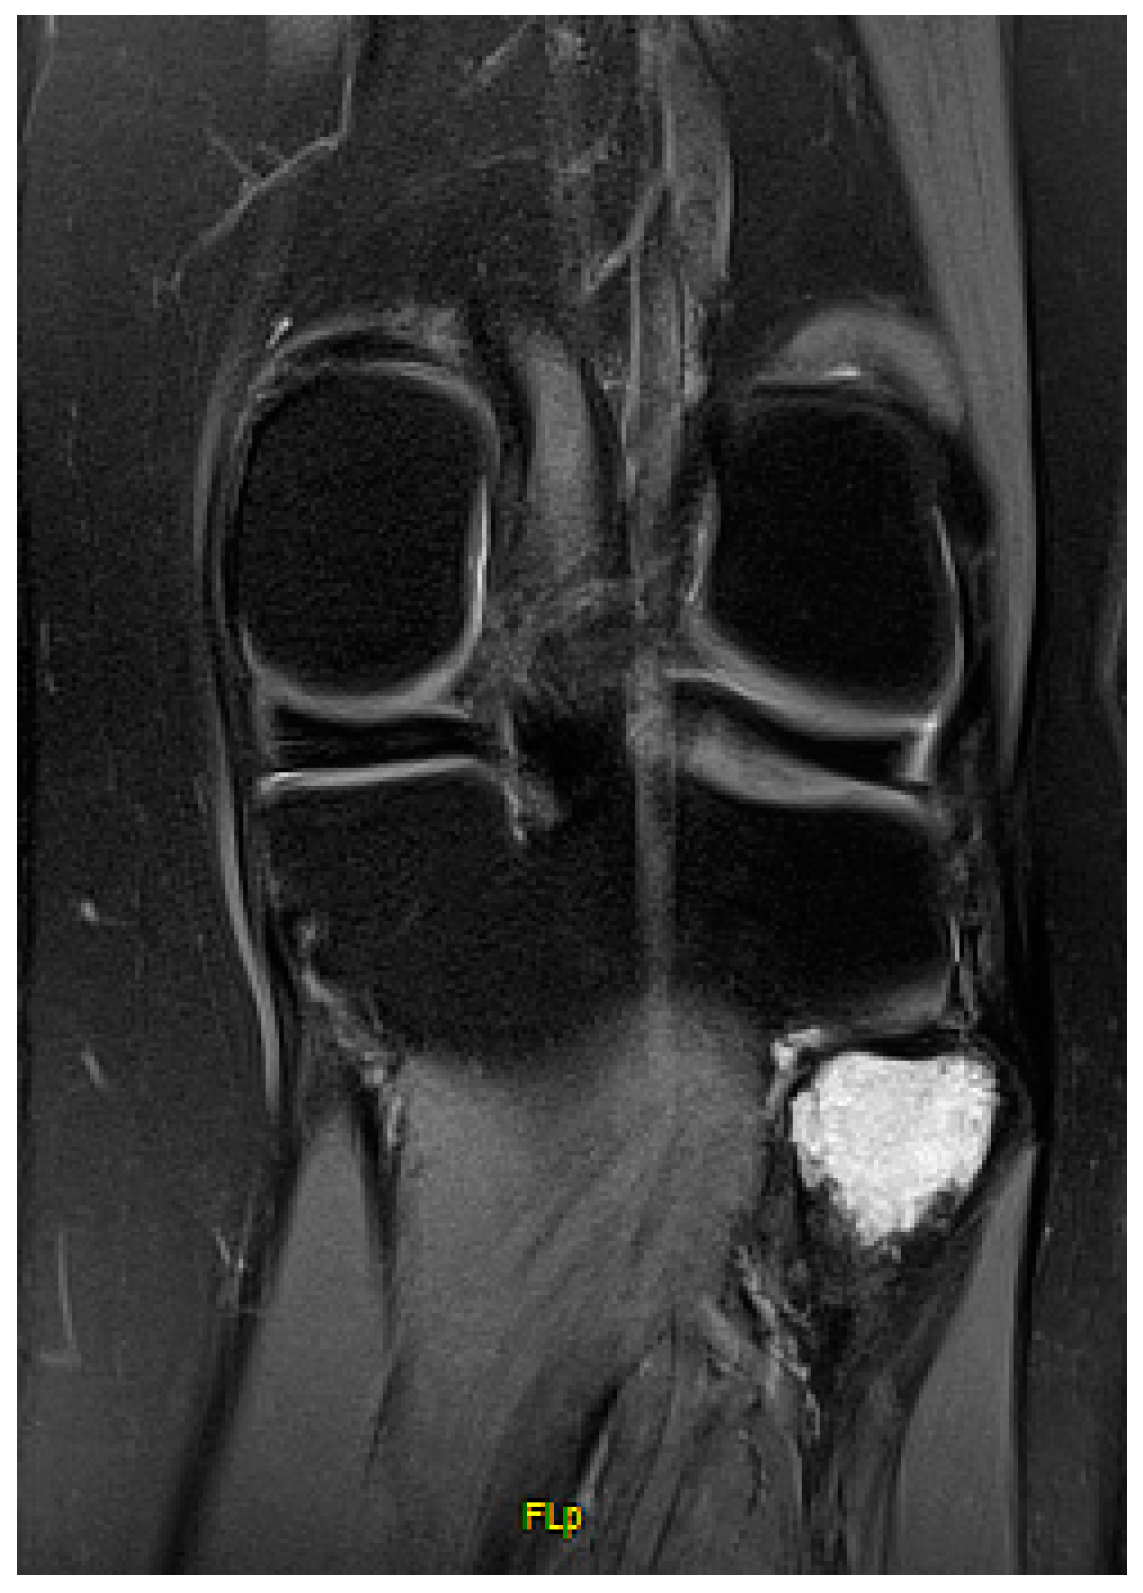

Proximal Fibula Resection for Tumors—Case Series and Technical Note

2. Methods